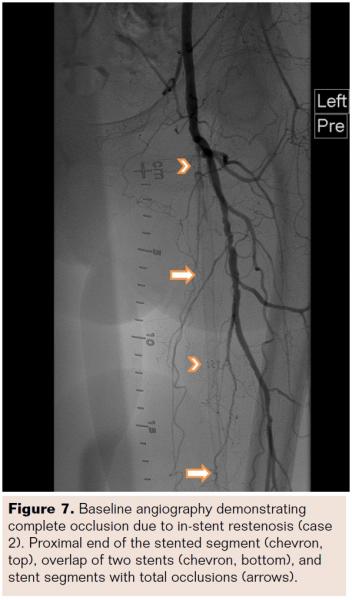

An 80-year-old black male with a history of hypertension, hyperlipidemia, and diabetes noted severe claudication in his right leg (Rutherford Class III; TASC A; ABI 0.86). The patient received a stent in the SFA 16 months prior. Angiography revealed reduced flow through the stented segment. Core laboratory adjudication measured 61% diameter stenosis, with a reference vessel diameter of 5.96 mm and a minimum lesion diameter of 2.32 mm (Figure 10). The lesion length was 29 mm within a 110 mm stent. Mild calcification was observed as well as a class 2 stent fracture (Figure 11). In the presence of a stent fracture, caution must be exercised since fractures increase the risk of suboptimal guidewire placement by sandwiching the guidewire between the stent and the vessel wall. Multiple angiographic views should be utilized to ensure proper guidewire placement. Stent fractures may impede the advancement of treatment devices, which may prolong procedure time and increase risk for vessel trauma, stent damage, and device damage. Stent fractures may also rupture PTA balloons, reducing treatment effectiveness and contributing to additional treatment time and cost.